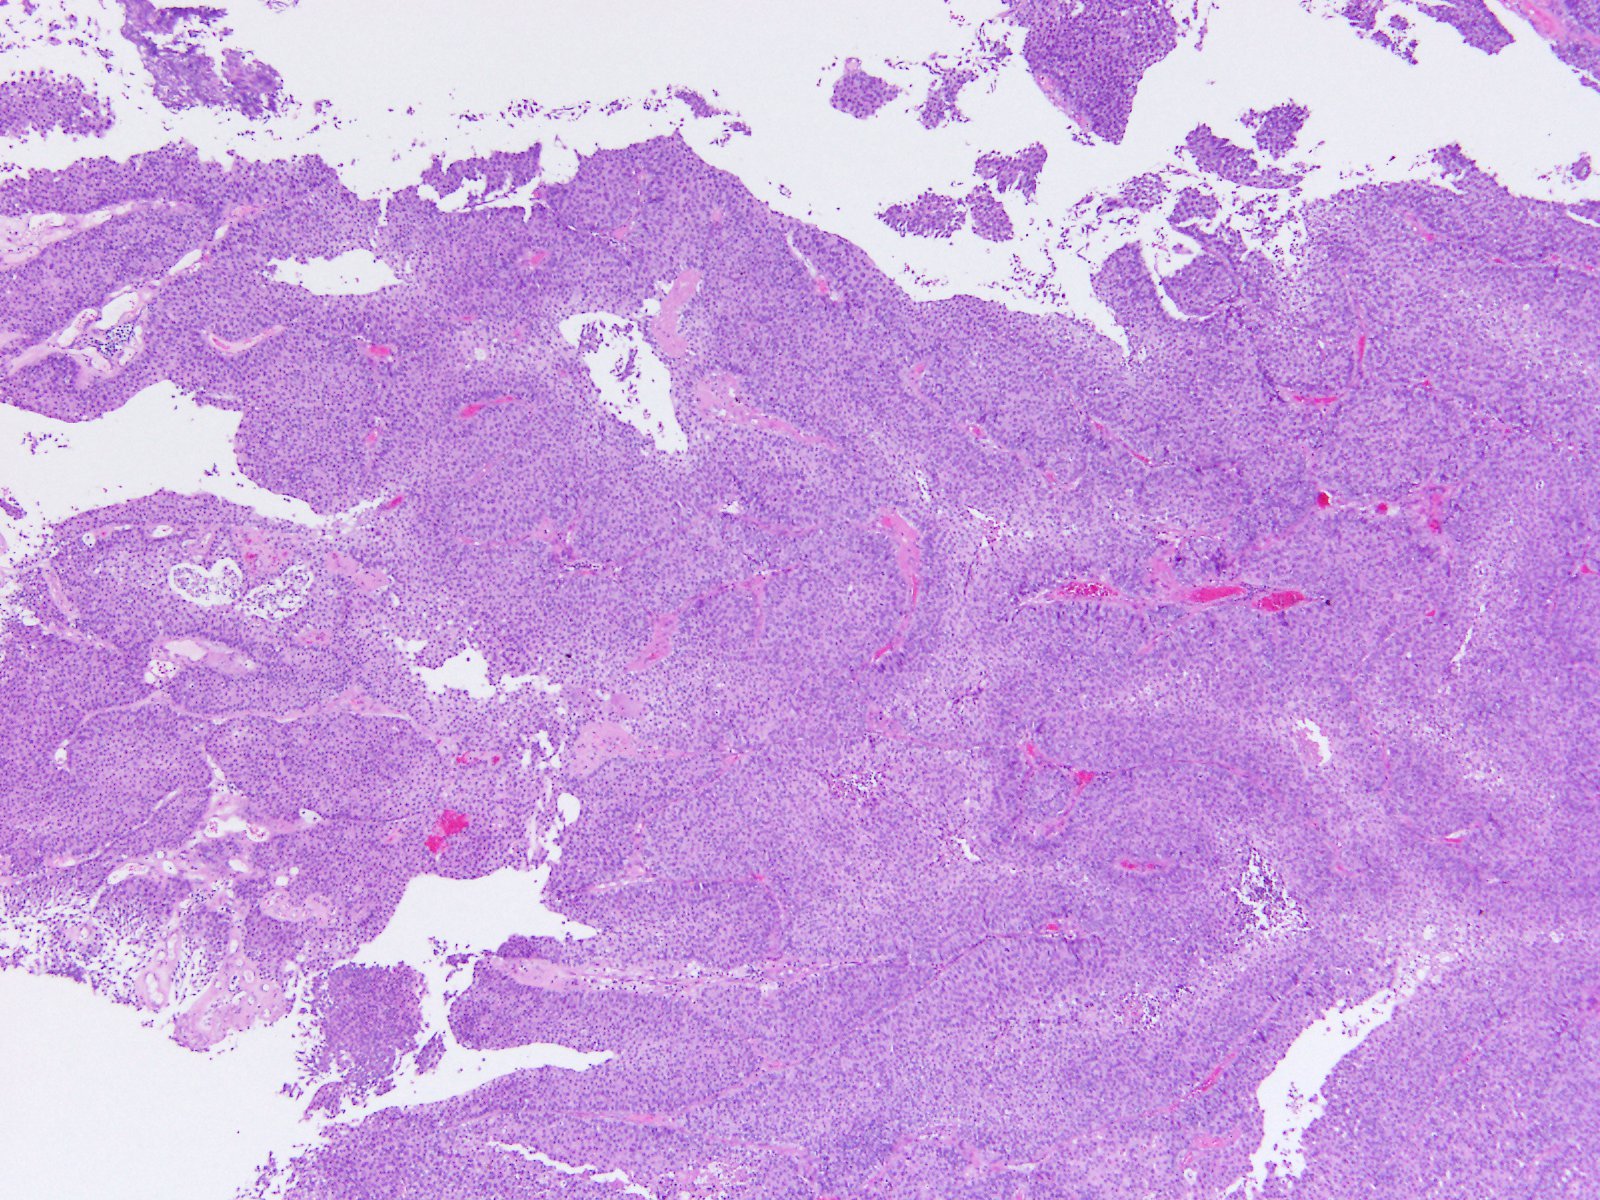

Consensus grade: High-grade papillary urothelial carcinoma (HG-PUC)

Case description (by case creator):

Papillary tumor in TUR-BT.